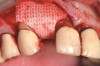

A full-thickness incision was made. Flap reflection revealed a narrow residual ridge with significant apical undercuts (Figure 8). Regenaform® paste (Exactech, Inc, Gainesville, FL) was molded on the buccal aspect of the ridge, as well as crestally. A 20-mm x 30-mm Ossix Plus membrane was trimmed and adapted to cover the graft material (Figure 9). Periosteal releasing incisions were made, and passive primary closure was obtained.

After 7 months of unremarkable healing, surgical re-entry revealed more than 10 mm of newly formed horizontal bone (Figure 10).

Figure 9  The Regena<i>form</i> paste molded to the ridge, and the Ossix Plus resorbable membrane ready for positioning over the graft material.

Figure 9

Figure 10  The reconstructed ridge, 7 months after surgery.

Figure 10